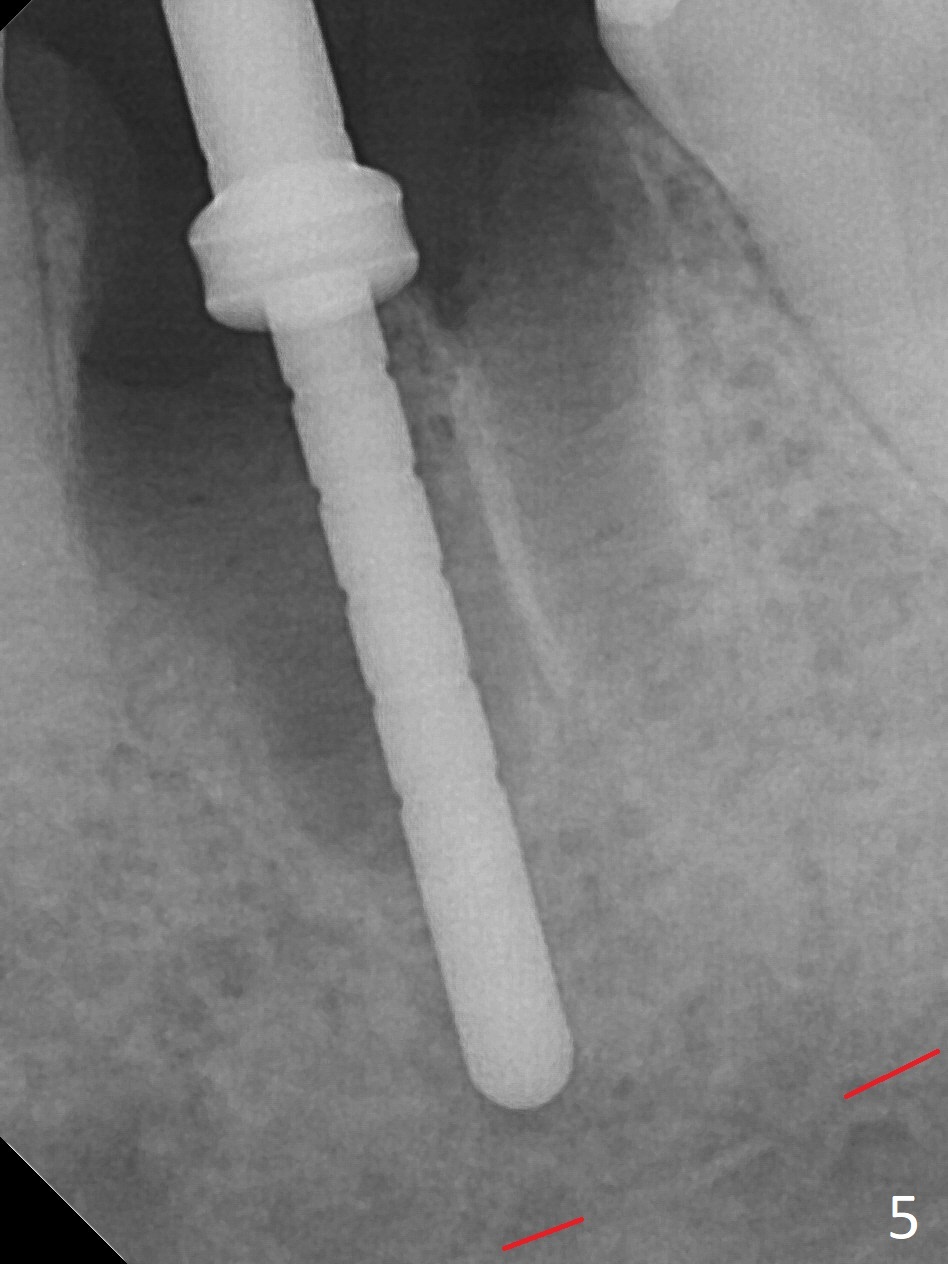

When the patient returns 9 months later, there is severe buccal gingival recession and abscess at #19 (Fig.1 *) with large mesial periradicular radiolucency (Fig.2 *). The septum is thin and the buccal crest is low after extraction (Fig.3 * (mesial root vertical fracture)). Osteotomy is initiated in the mesial socket immediately against the septum (Fig.4.5) with ~ 5 mm in the native bone. Due to severe buccal plate resorption, a shorter implant is placed (Fig.6; 5x15 mm in stead of 18 mm). There is at least 2 mm gap buccally for Vanilla Graft, which is also placed next to the implant and the neighboring root (Fig.7 *). There is clearance from the Inferior Alveolar Canal (Fig.8 red dashed line). Both the mesial and distal sockets heal 5.5 months postop (Fig.9), although the apical portion of the distal socket was not filled with allograft (Fig.7). The implant was placed mesial. The straight abutment (6.5x4(4) mm) (Fig.10) is changed to an angled one (5.5 x15 degrees 3 mm cuff (Fig.11)) before impression. The implant is also placed buccally. Therefore the implant position is far more important than its length. The abutment is retightened 2.5 months post cementation, which is related to mesiobuccal placement of the implant (Fig.12). An ideal trajectory is determined by drawing 2 horizontal lines (at crestal and apical levels: red lines in Fig.13), finding a central point of each line (vertical short line) and joining these 2 central points (Fig.14 pink line). In fact the ideal osteotomy should have been established distal to the septum in this case. Guided surgery may alleviate the issue. The crown is not loose, but the patient feels that the implant tooth cannot sustain mastication. In fact the screw is removed with hand driver (not wrench). The abutment hex is rounded and worn. A new 5.5x4(4) mm abutment is placed (without knowledge of previous use of an angled abutment) with mesial reduction to reduce undercut and buccodistal margin lowered to reduce gingival embrasure. It is that the straight abutment could decrease the chance of screw loosening. Otherwise the implant has to be removed for better trajectory.